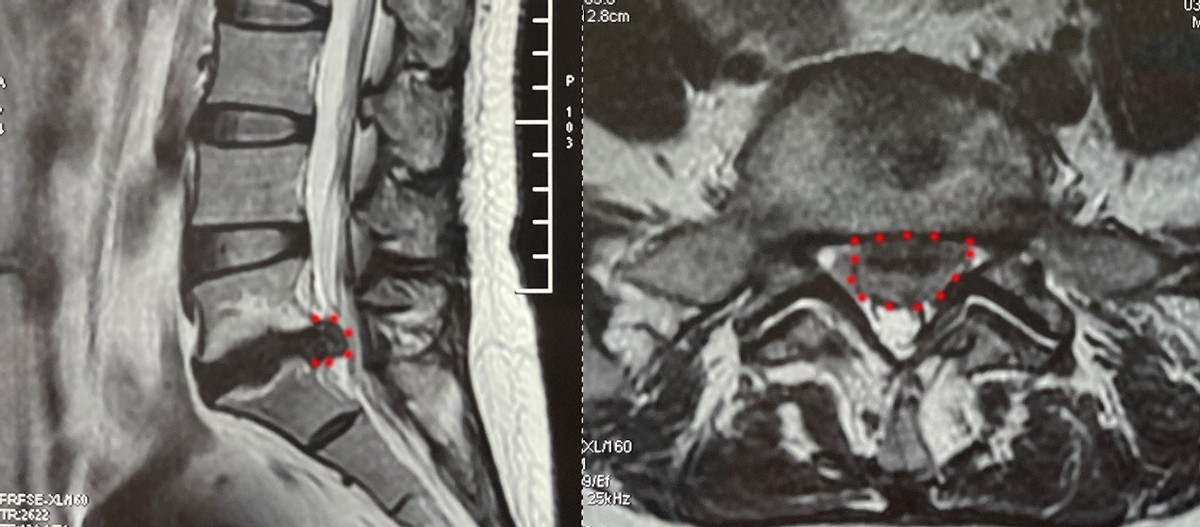

脊柱病医院颈椎病区董亮副主任医师接诊后,结合病史及检查结果,匡大姐腰椎间盘突出症诊断明确,且脱出髓核占到椎管的80%以上,属于巨大型椎间盘脱出,需要尽快手术。结合以往的经验和医院先进的微创手术系统,可以进行椎间孔镜微创手术。

但是患者椎间盘脱出巨大,神经严重受压,术中稍有不慎就会有神经损伤的风险;而且患者椎间盘突出属于中央脱出型,从一侧入路清除干净脱出的椎间盘具有较大难度,以上无疑对术者技术提出了很高的要求。

患者住院后,在脊柱病医院郝定均院长、颈椎病区孙宏慧主任、董亮副主任医师和其他专家的讨论下,为匡大姐制定了最为完善的手术方案。完善各项检查后,入院第2天,董亮副主任医师立即为患者实施了椎间孔镜下微创髓核摘除术+纤维环成形术。术中见到神经根变异,可见双神经根,进一步增加了手术难度。但是最终在不损伤神经的情况下,全部取出了压迫神经的大量脱出髓核组织,术中出血10ml,手术切口仅有7毫米。术后当天,匡大姐就戴着腰围下地活动,没有明显不适,腿部疼痛完全缓解。